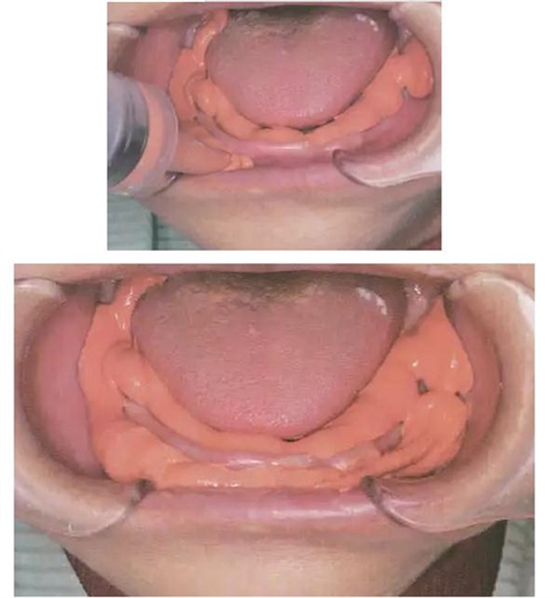

④ 輕體注入口內(nèi)

⑴用棉球擦干唾液

⑵ 用注射器將輕體印模材從左下磨牙后墊區(qū)開始,

沿著下頜舌骨肌后窩區(qū)經(jīng)過口底舌下區(qū)

至右下磨牙后墊區(qū)注射輕體。

⑶ 然后,從右下磨牙頰粘膜皺褶區(qū)開始,

沿著頰唇側(cè)直至左下磨牙頰粘膜皺褶區(qū)注射輕體。

⑤ 重體托盤口內(nèi)就位

⑴ 平穩(wěn)地放入,將前牙部分壓向牙槽脊,將托盤的舌側(cè)翼緣區(qū)伸入下頜舌骨肌后窩區(qū),讓患者舌頭放在托盤上,并將托盤輕輕壓向下頜牙槽嵴,不可像傳統(tǒng)托盤大力壓向牙槽嵴,下頜牙槽嵴條件差時(shí),輕輕將托盤壓向牙槽嵴7-10秒后再要求患者閉上嘴,用嘴唇含住托盤柄。

⑵ 術(shù)者站在患者后方,用手輕輕推頰棚區(qū)向上。

以避免多余印模材在頰棚區(qū)滯留。